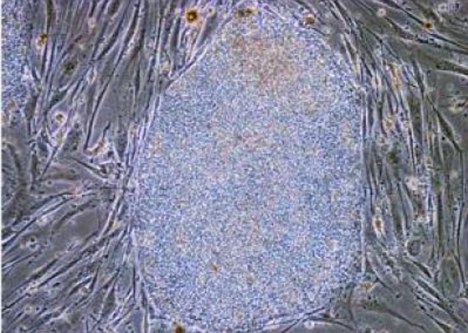

顯微鏡下的特異性“殺手”T細(xì)胞,研究人員認(rèn)為該細(xì)胞能被直接注射到癌癥患者體內(nèi)來進(jìn)行輔助治療。

據(jù)研究人員透露,“殺手”T淋巴細(xì)胞自然存在于人體內(nèi),但由于其數(shù)量很少,而且存活時間較短,所以利用其治療癌癥幾乎不可能。理化學(xué)研究所的科學(xué)家們?yōu)榱俗孴淋巴細(xì)胞獲得持久的殺傷能力,他們在實驗中對該細(xì)胞進(jìn)行重新編碼,誘導(dǎo)其成為另一種細(xì)胞——多功能干細(xì)胞(簡稱“iPS細(xì)胞”),隨后科學(xué)家再利用iPS細(xì)胞生成具有完全活性的、存活時間較長的“殺手”T淋巴細(xì)胞,大大提高了其殺死癌細(xì)胞的可能性。